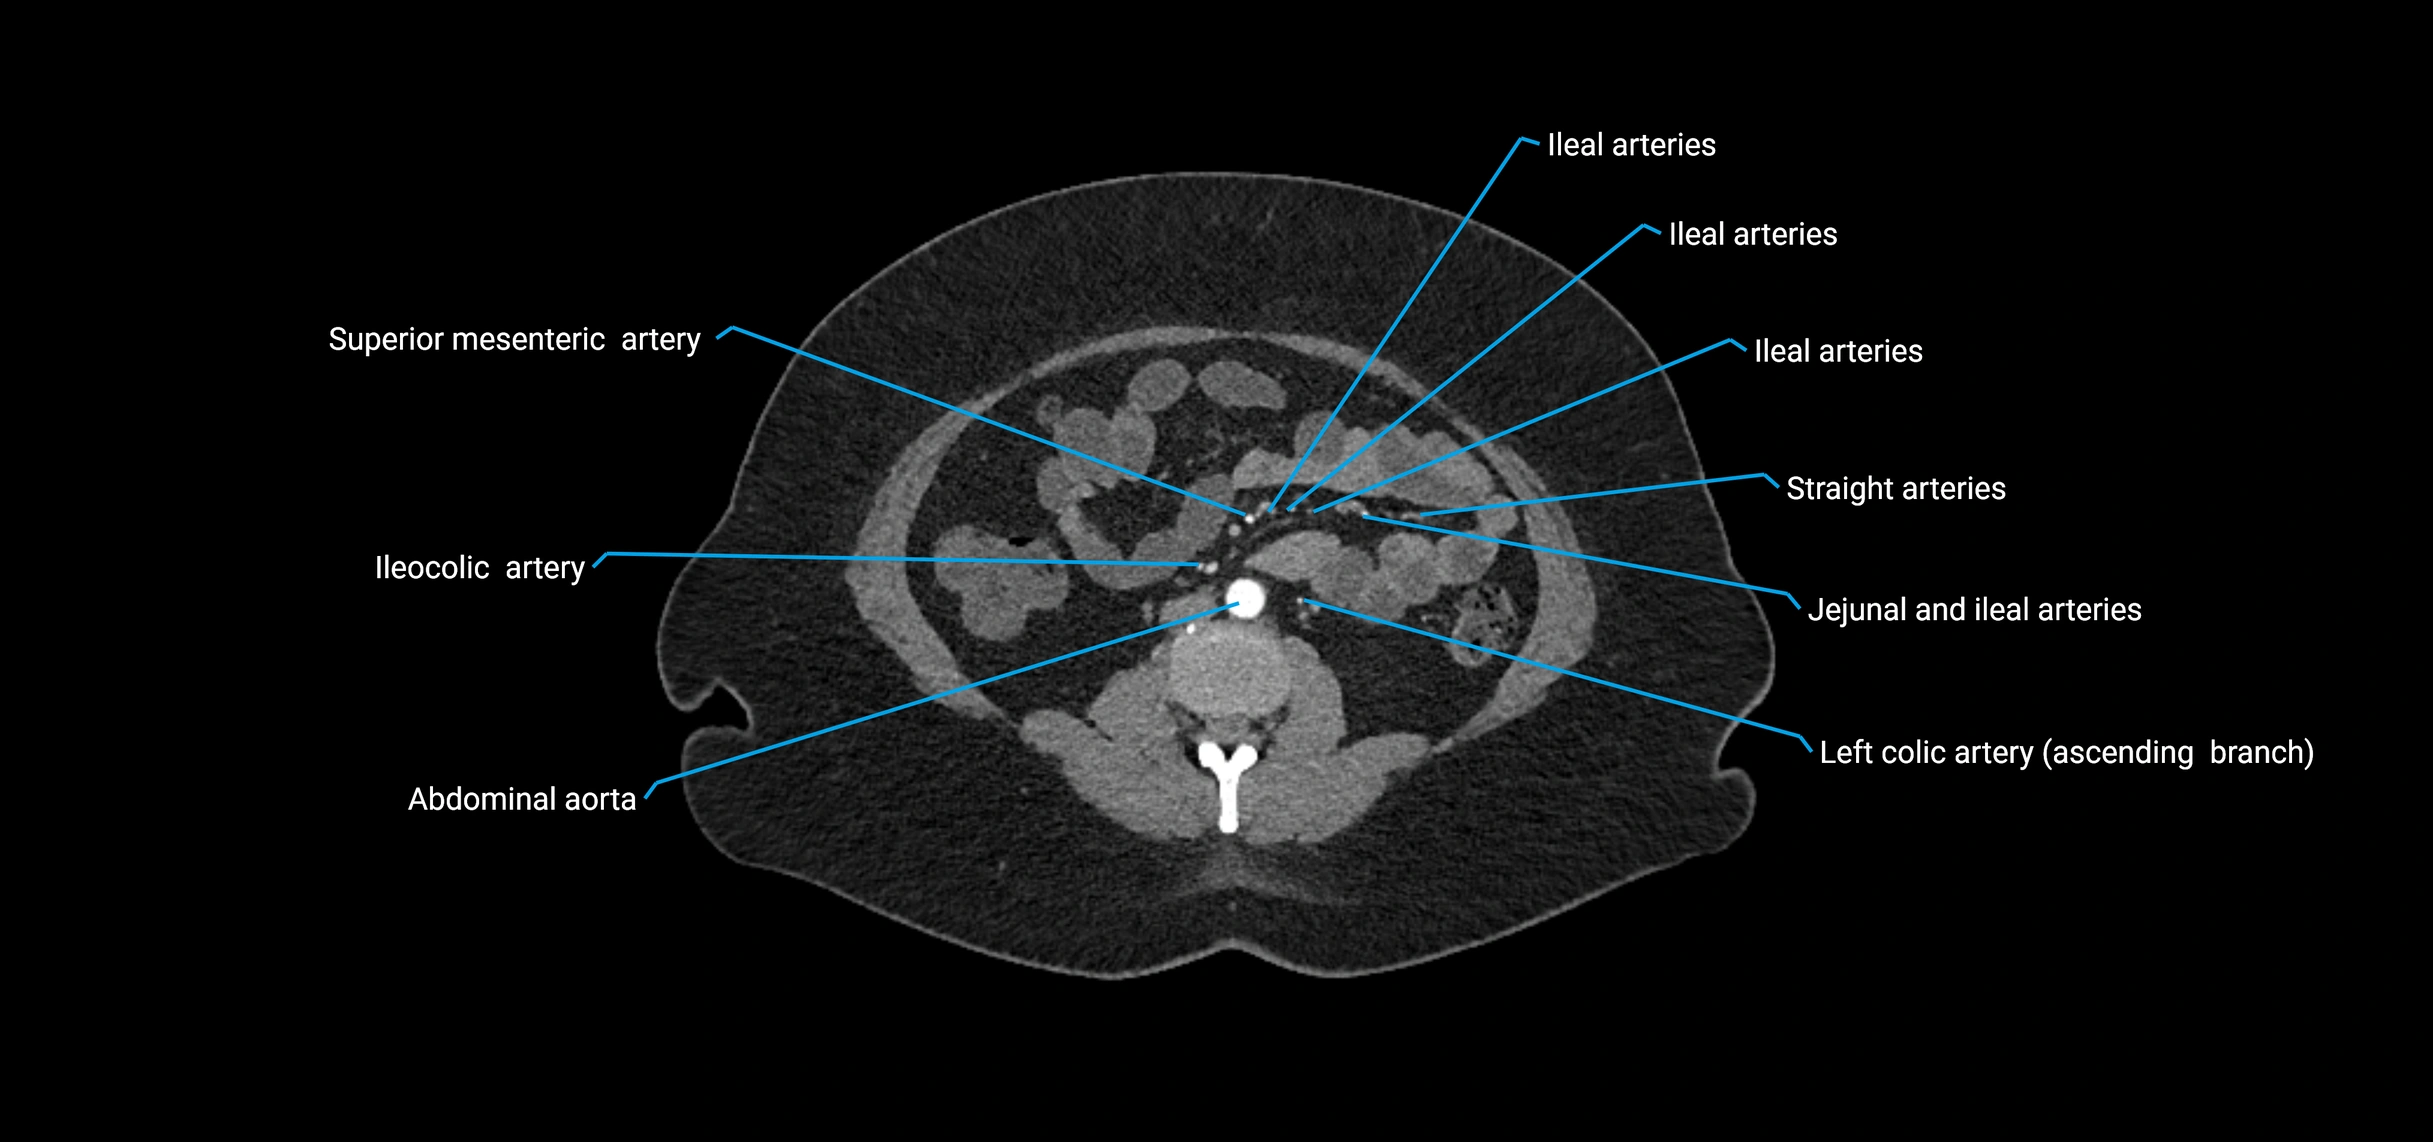

Contrast-enhanced CT (CTA):

• Gold standard for abdominal aortic imaging

• Provides excellent detail of lumen, wall, aneurysm, thrombus, and branch vessels

• Multiplanar and 3D reconstructions help in aneurysm measurement, stent graft planning, and dissection evaluation

• Detects acute rupture, traumatic injury, or occlusion with high sensitivity